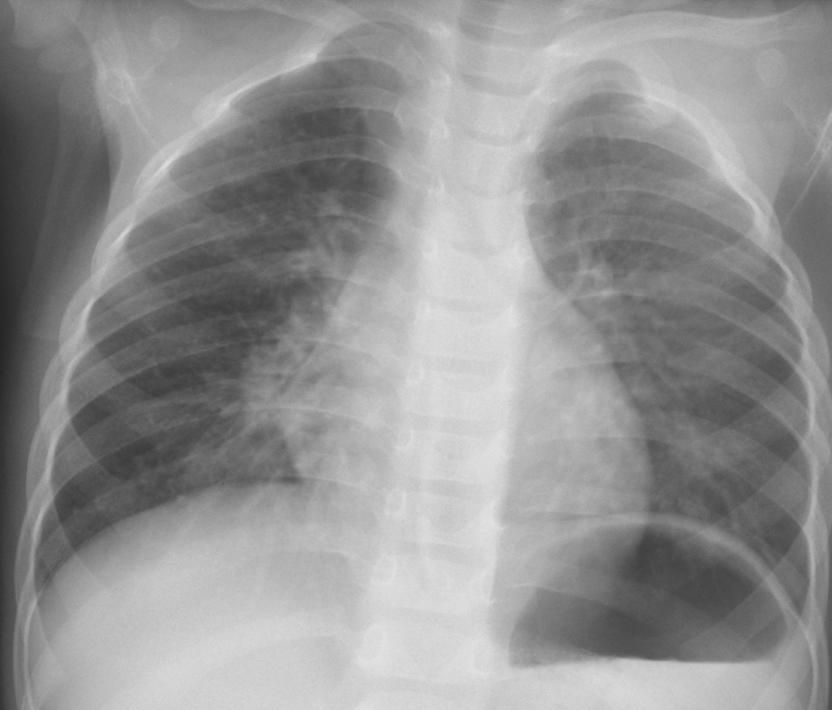

左肺野にスリガラス様陰影をみとめる肺炎の2症例、症例左は迅速抗原検査(COV-2)陰性抗体検査SERS-C-2 COI 陽性。右はCOV-2陽性。